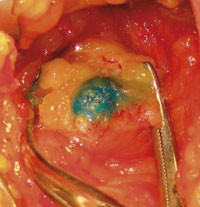

Vaktpostlymfeknuten identifiseres ved injeksjon av radiokolloid og/eller fargestoff. Etter periareolær injeksjon går radiokolloidet inn i lymfekar og konsentreres i vaktpostlymfeknuten. Preoperativt lymfoscintigram viser om det er opptak av radioaktivitet i lymfeknutene (fig 1), og ved hjelp av geigerteller kan lymfeknuten(e) identifiseres peroperativt. Blåfargen injiseres peritumoralt eller subkutant i øvre laterale kvadrant av brystet. Den bindes til albumin (2) og føres via lymfekar til lymfeknuten(e) som farges blått/grønt (fig 2). Det mest brukte fargestoffet i Norge er patentblått V (Patent blue V).